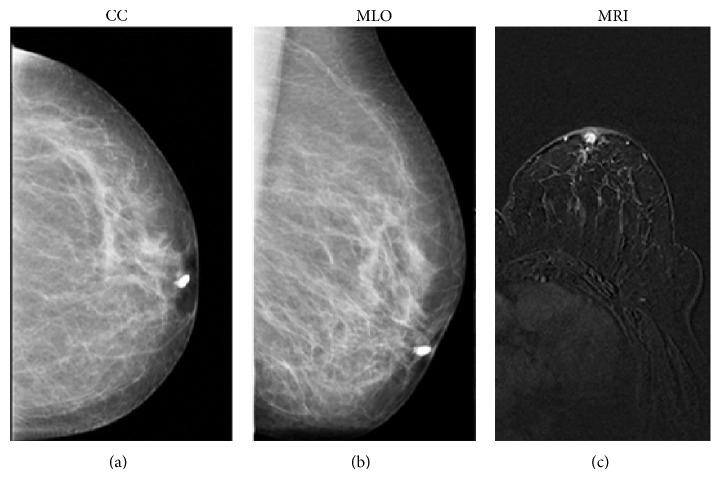

Breast MRI in patients with unilateral bloody and serous-bloody nipple discharge: a comparison with galactography.

Retrospective study including 53 unilateral discharge patients who performed galactography and MRI. We evaluated the capability of both techniques in identifying pathology and distinguishing between nonmalignant and malignant lesions. Lesions BIRADS 1/2 underwent follow-up, while the histological examination after surgery has been the gold standard to assess pathology in lesions BIRADS 3/4/5. The ROC analysis was used to test diagnostic MRI and galactography ability.

After surgery and follow-up, 8 patients had no disease (15%), 23 papilloma (43%), 11 papillomatosis (21%), 5 ductal cancer in situ (10%), and 6 papillary carcinoma (11%) diagnoses. Both techniques presented 100% specificity; MRI sensitivity was 98% versus 49% of galactography. Considering MRI, we found a statistical association between mass enhancement and papilloma (P < 0.001; AUC 0.957; CI 0.888-1.025), ductal enhancement and papillomatosis (P < 0.001; AUC 0.790; CI 0.623-0.958), segmental enhancement and ductal cancer in situ (P = 0.007; AUC 0.750; CI 0.429-1.071), and linear enhancement and papillary cancer (P = 0.011).

MRI is a valid tool to detect ductal pathologies in patients with suspicious bloody or serous-bloody discharge showing higher sensitivity and specificity compared to galactography.